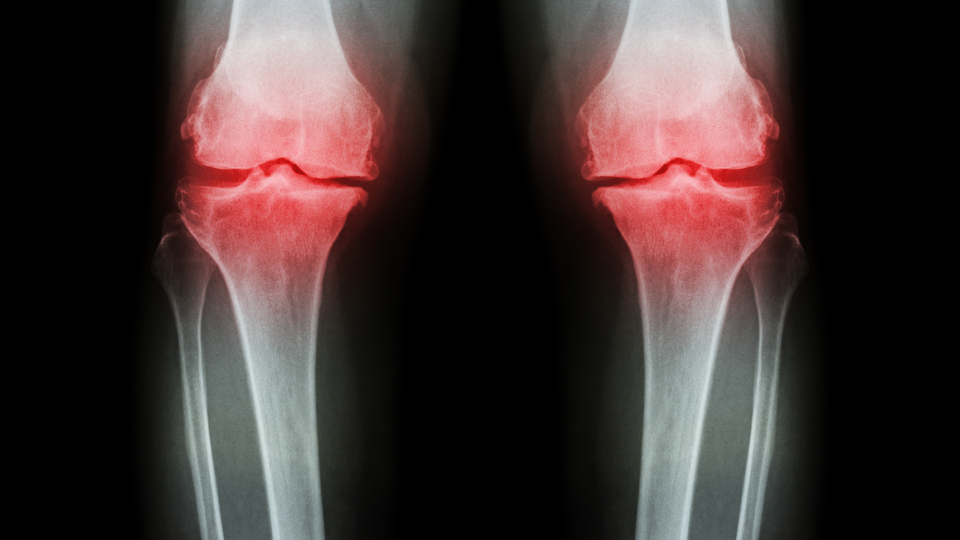

Daha az kemik dokusuna sahip oldukları için kadınların erkeklere göre osteoporoza yakalanma riski daha yüksektir. Kemik kalitesi ve yoğunluğunun azalması ile kemiklerin kırılgan hale gelmesine neden olan osteoporozu (kemik erimesi) doğru beslenme ile durdurmak ya da önlemenin mümkün olduğunu söyleyen Ortopedi ve Travmatoloji Uzmanı Prof. Dr. Çağatay Öztürk anlattı.

Osteoporoz vücudumuzda en çok omurgamızı etkiler. Osteoporotik kemiklerdeki kırıklar sıklıkla omurga, kalça ve el bileğini içerir. Kalça ve el bileğindeki osteoporotik kırıkların aksine omurgadaki kırıklar sıklıkla düşme veya travma ile ilişkili değildir. Vücutta sessizce ilerleyen ve kırık oluşmadığı sürece belirti vermeyen osteoporoz vakalarının sadece yüzde 30’u klinik şikayetler ile belirlenirken, geri kalan kısmın çoğu rastlantısal olarak saptanıyor. Hastalığın yaygın bulguları ise bel ve sırt ağrıları, boyda kısalma, omurgada kırık, sırtta kamburlaşma olarak ortaya çıkıyor.